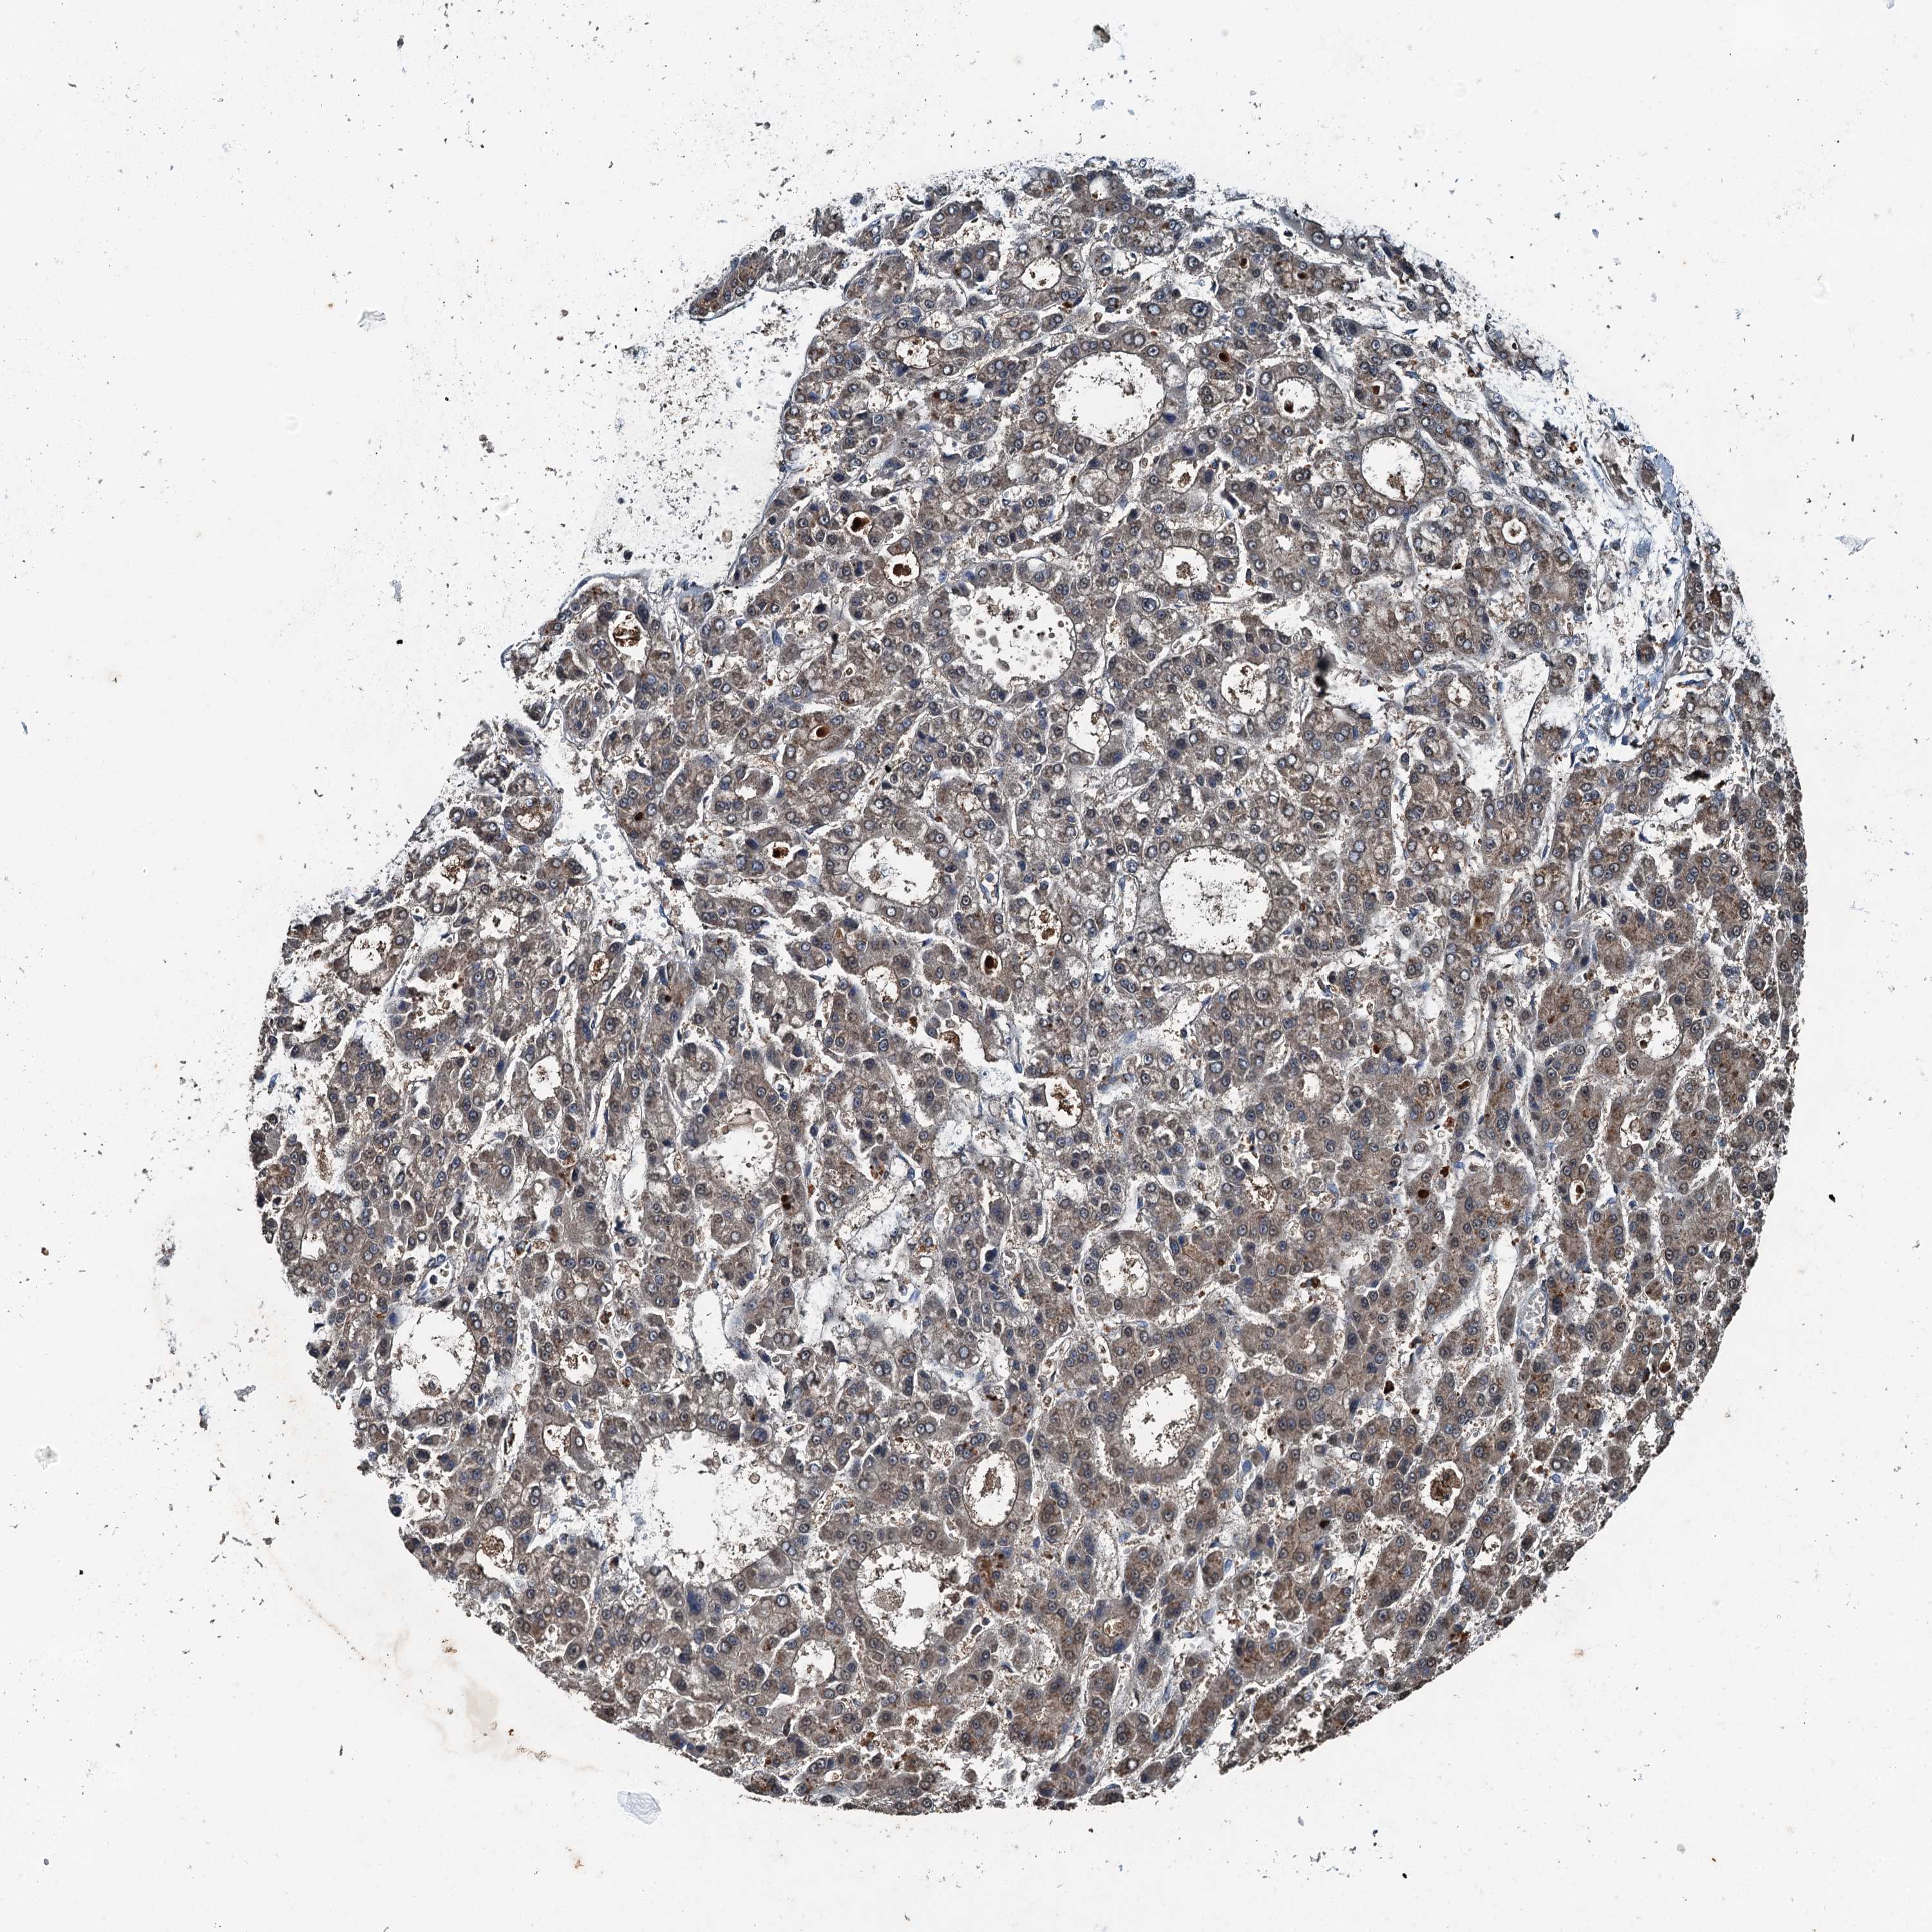

LIVER CANCER - Protein expressioni

A mouse-over function shows sample information and annotation data. Click on an image to view it in a full screen mode. Samples can be filtered based on level of antibody staining by selecting one or several of the following categories: high, medium, low and not detected. The assay and annotation is described here.

Note that samples used for immunohistochemistry by the Human Protein Atlas do not correspond to samples in the TCGA dataset.

Antibody stainingi

Antibody staining in the annotated cell types in the current human tissue is reported as not detected, low, medium, or high, based on conventional immunohistochemistry profiling in selected tissues. This score is based on the combination of the staining intensity and fraction of stained cells.

Each image is clickable and will lead to virtual microscopy that enables deeper exploration of all samples and also displays staining intensity scores, fraction scores and subcellular localization as well as patient and tissue information for each sample.

Antibody HPA039687

Antibody HPA040036

Staining

High

Medium

Low

Not detected

Intensity

Strong

Moderate

Weak

Negative

Quantity

>75%

75%-25%

<25%

None

Location

Nuclear

Cytoplasmic/membranous

Cytoplasmic/membranous,nuclear

Cholangiocarcinoma

Carcinoma, Hepatocellular, NOS